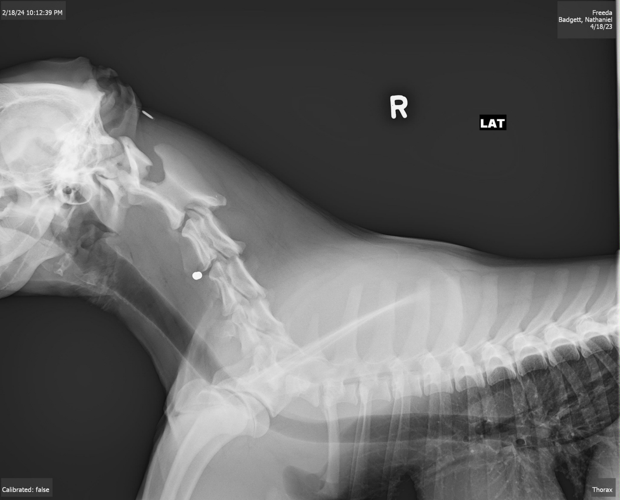

Cpl. Hunter Morrow said when the family "ran outside they seen the blood on the ground. They had rushed the dog to a nearby hospital and had multiple X-rays and the X-rays did reveal what looked like a .22 long rifle bullet in his neck."

A picture of an X-ray image shows the bullet apparently lodged near the vertebrate in the dog's neck area. Morrow said the dog is expected to survive, but has a long road to recovery.

The dog that was poisoned is still recovering. Freeda came home the same night she was shot. Badgett said the bullet is still lodged in her neck, and she is at risk for paralysis.